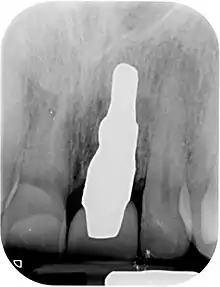

X-ray of root analogue dental implant two rooted left lower molar.jpg